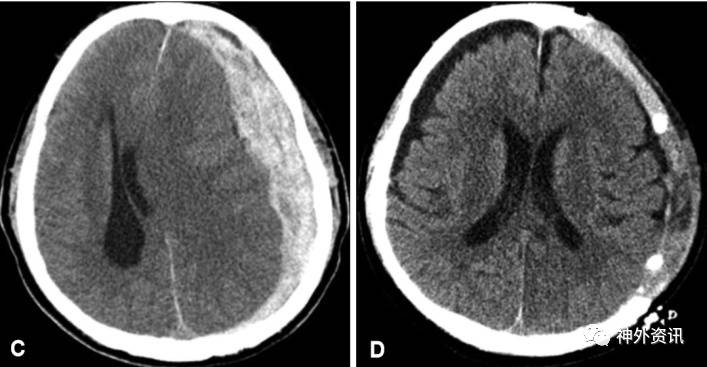

术前可见慢性硬脑膜下血肿量很大

阶梯性减压治愈亚急性硬膜下血肿一例丨颅脑创伤神经重症病例周刊95期